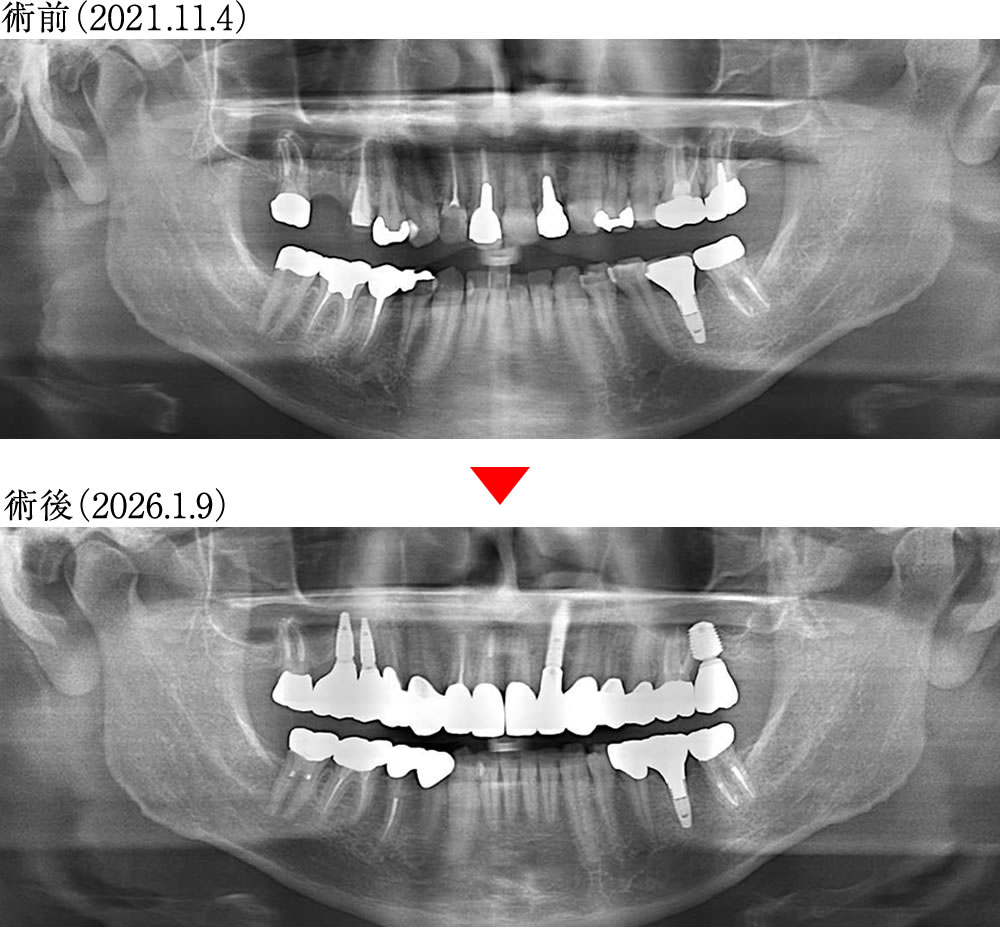

術前術後のレントゲン画像

インプラントとジルコニアセラミックにより、審美性と機能性が改善され、しっかり噛める状態になりました。

こちらの患者さまは、保存不可能な歯を抜歯後にインプラント治療を行い、古い金属の詰め物や被せ物は、ジルコニアセラミックにて治療する計画を立てました。

| リスク | 治療中の仮歯での噛みにくさ、インプラントの外科手術による腫れや痛み。 |